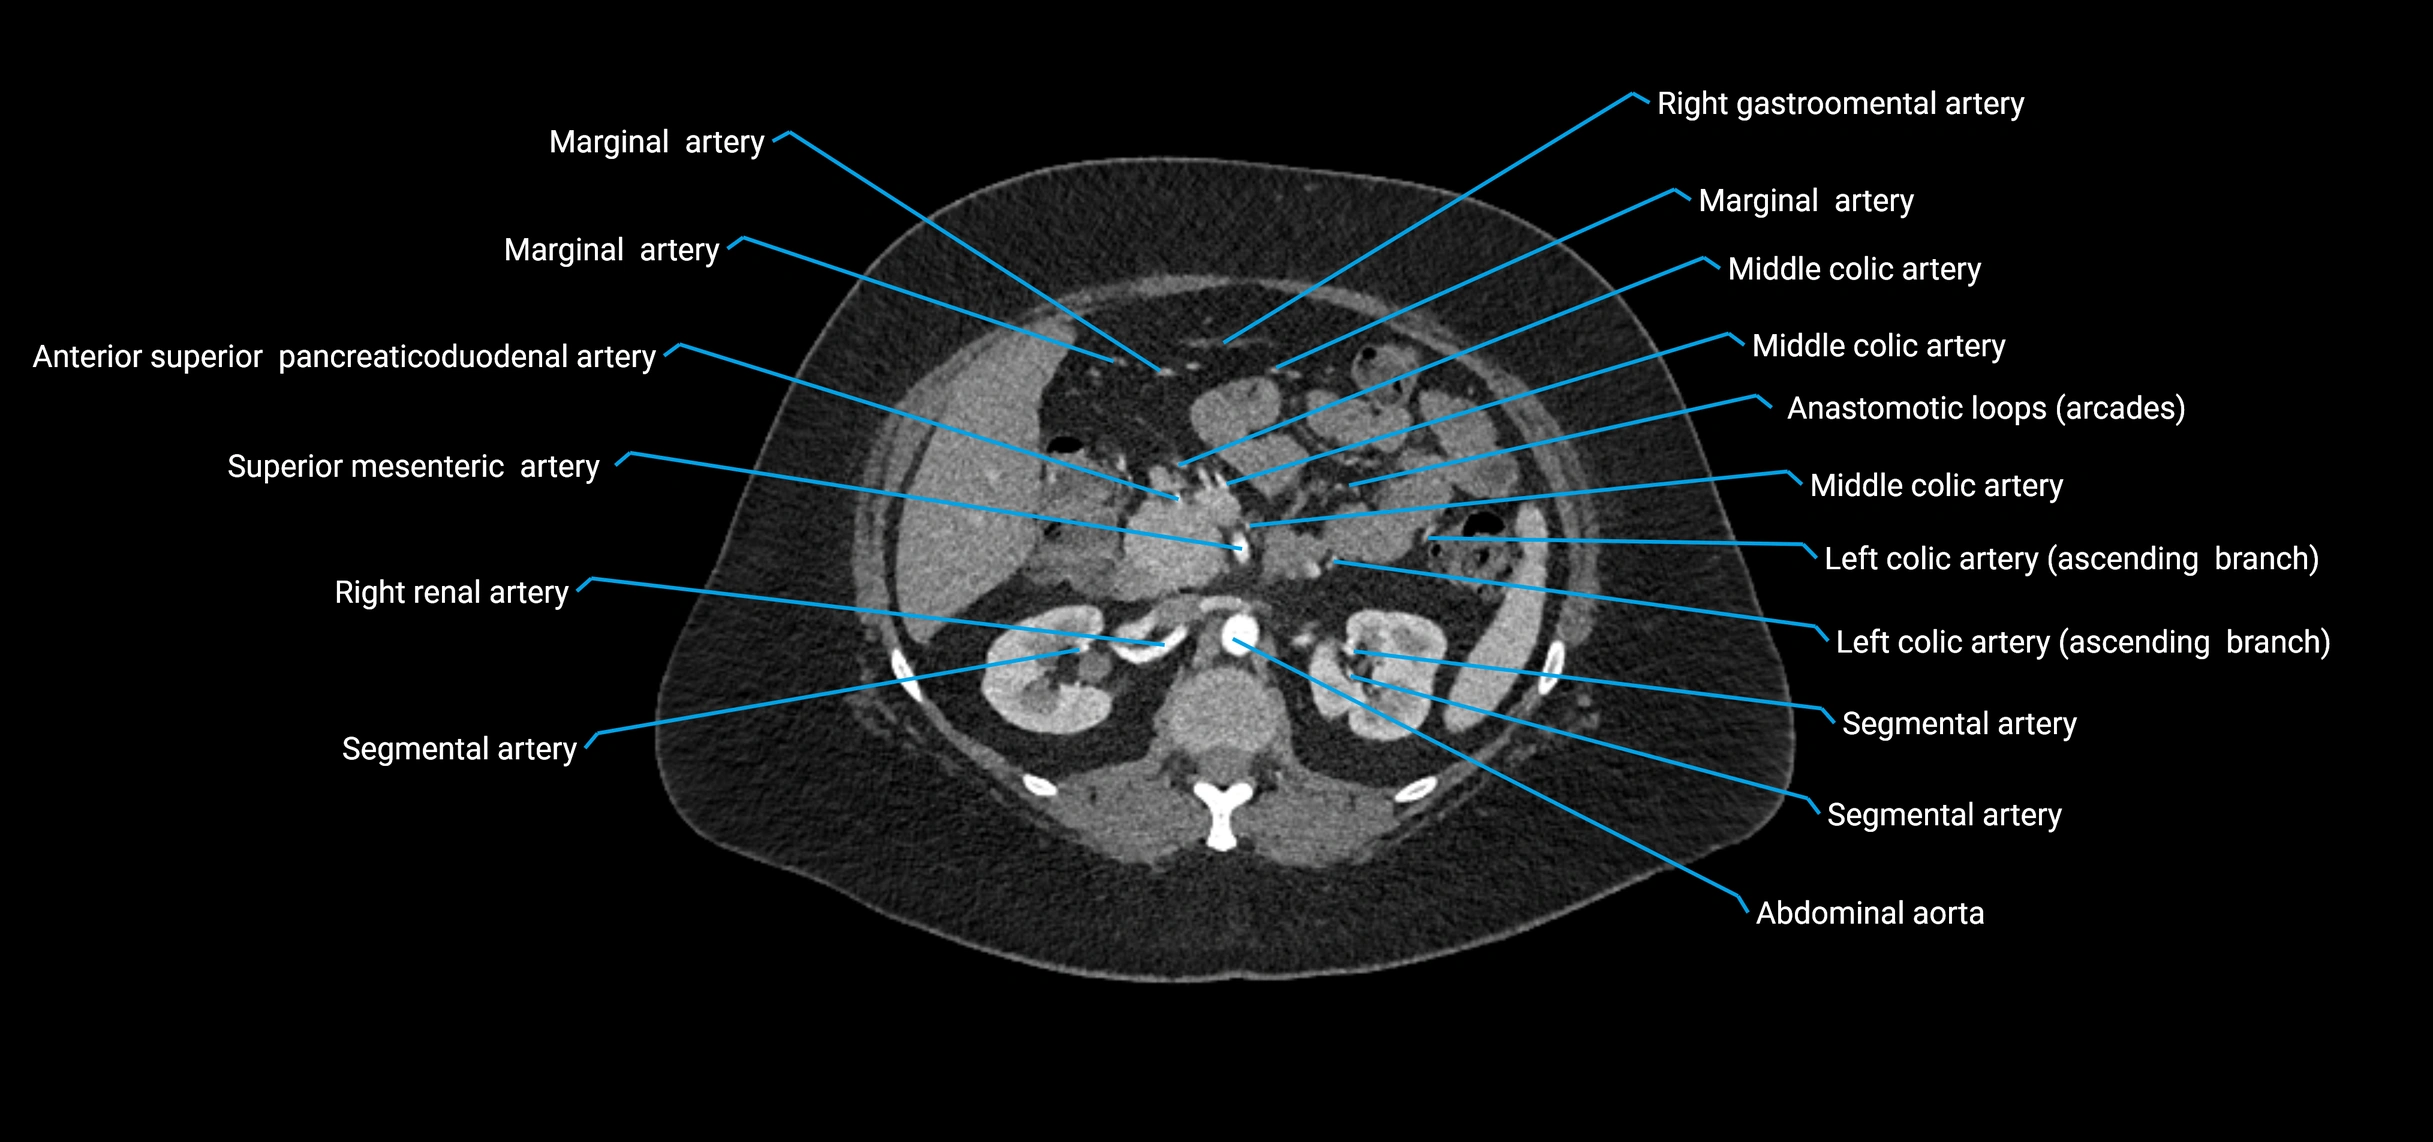

Contrast-enhanced CT (CTA):

• Gold standard for abdominal aortic imaging

• Provides excellent detail of lumen, wall, aneurysm, thrombus, and branch vessels

• Multiplanar and 3D reconstructions help in aneurysm measurement, stent graft planning, and dissection evaluation

• Detects acute rupture, traumatic injury, or occlusion with high sensitivity